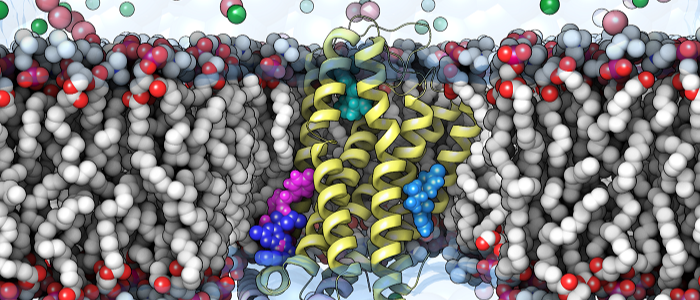

New research discovery could advance drug treatments for diabetes and obesity